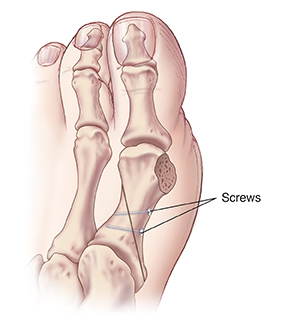

Base osteotomy

With this procedure, a wedge of bone is removed from the first metatarsal bone. This is farther back than in the head chevron osteotomy. The bone is moved closer to the second metatarsal bone. It's held together with screws or a plate. The bony bump is also removed. Your foot may be placed in a cast, shoe, or boot to heal correctly. You may be asked not to bear weight on this foot for a few weeks.